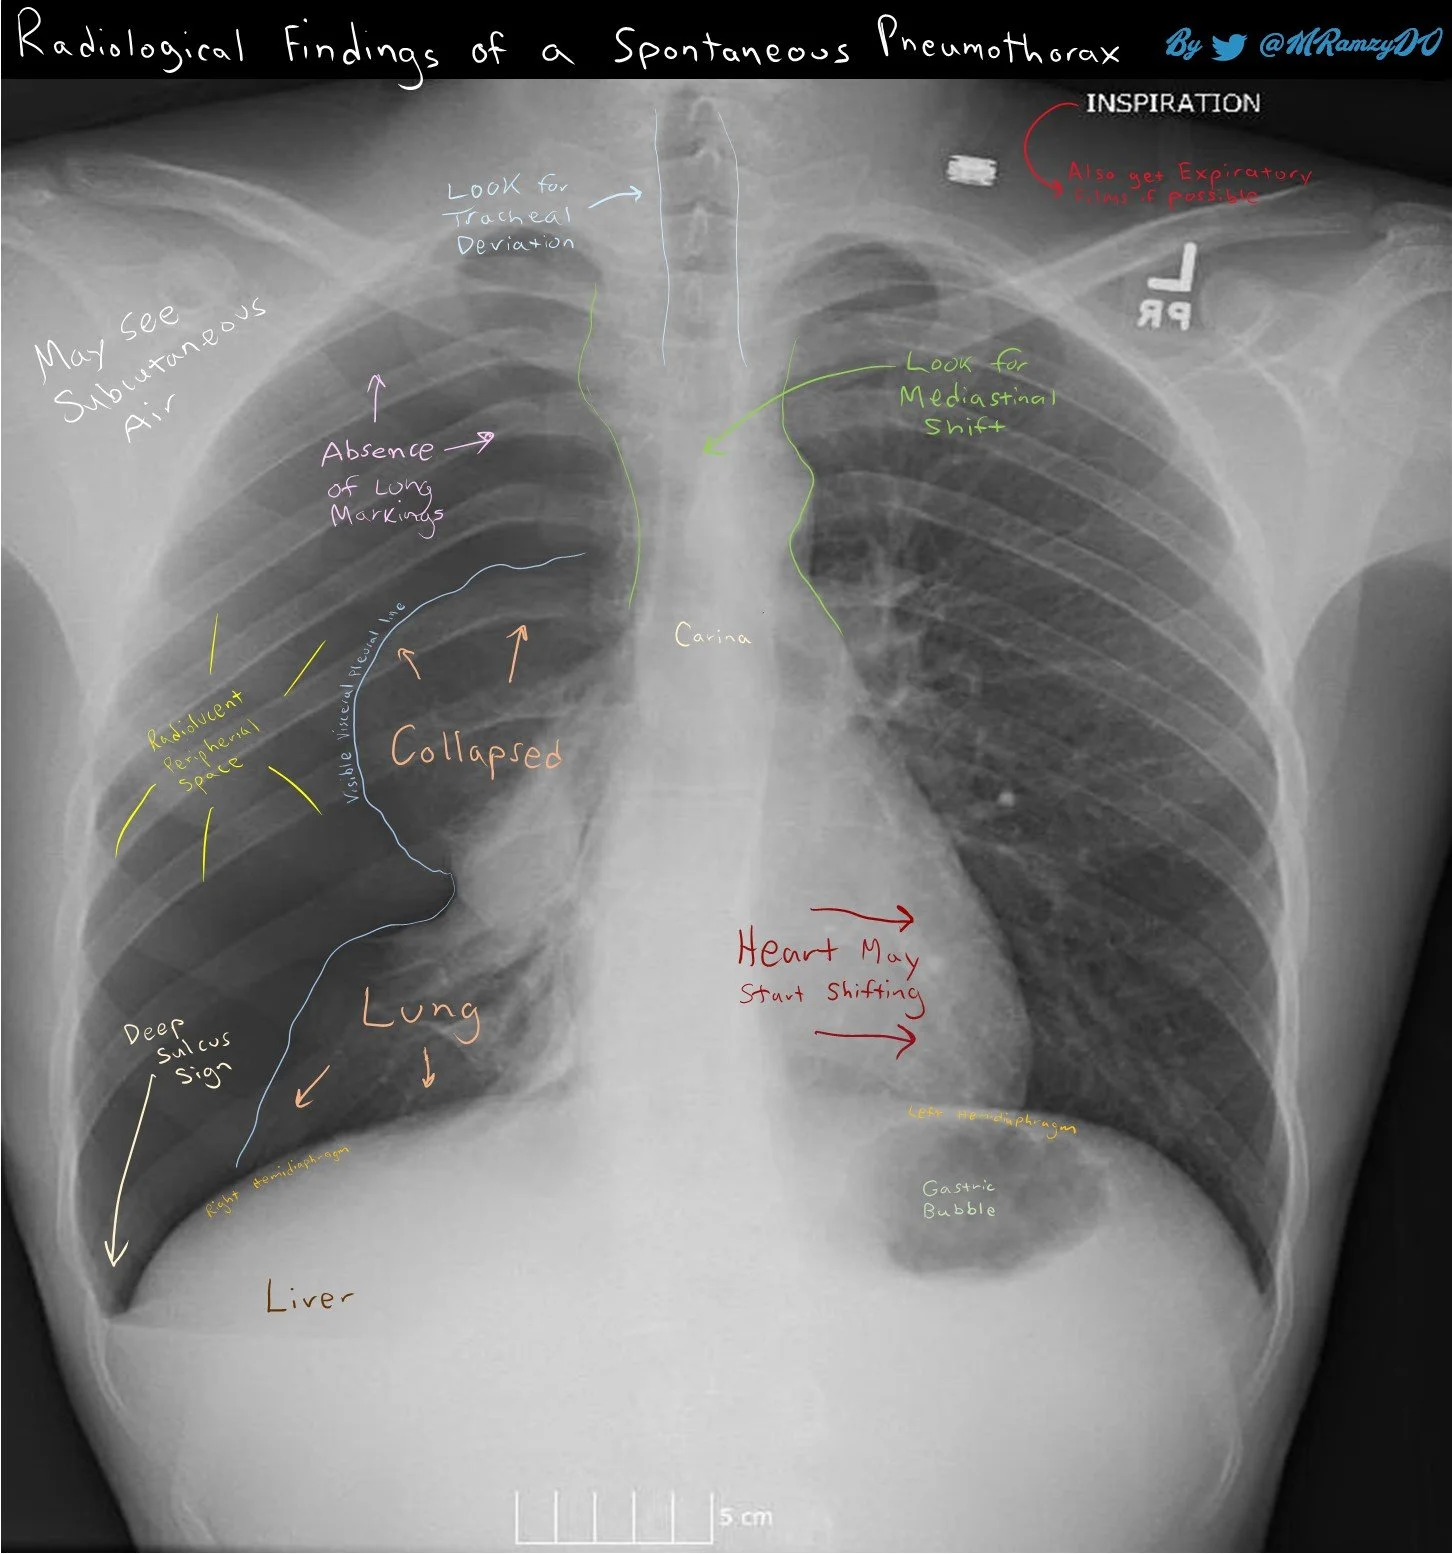

X-Ray Findings of Pneumothorax May 28 Written By Mark Ramzy If planning to use elsewhere for educational purposes, please cite credit to Dr. Mark Ramzy, DO Mark Ramzy